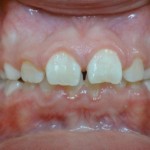

Photos avant et après traitement par Bielle

Vue de Face